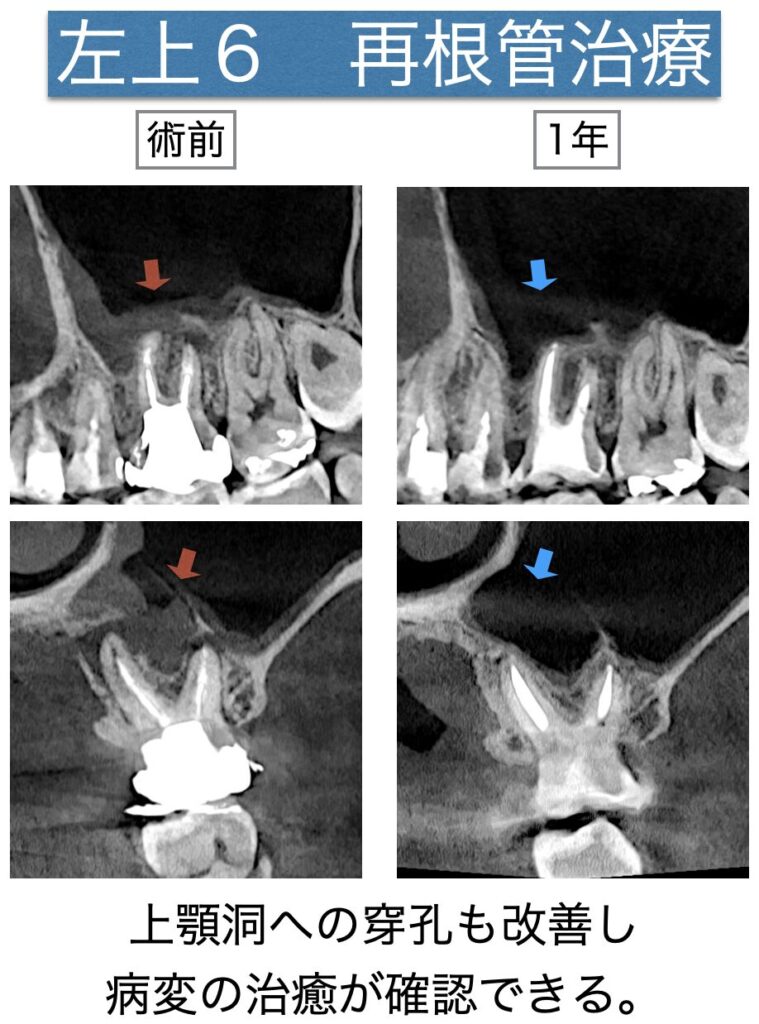

左上6の診査診断を行ったところMB・DB・P根尖に病変ができており、上顎洞への病変の交通が確認できました。

経過観察(1年)

その後、術後3ヶ月の時点の経過観察で臨床症状もなく病変の縮小傾向が見られたため、最終補綴へ移行していただくことになりました。

術後1年の経過観察では、病変が治癒しておりました。